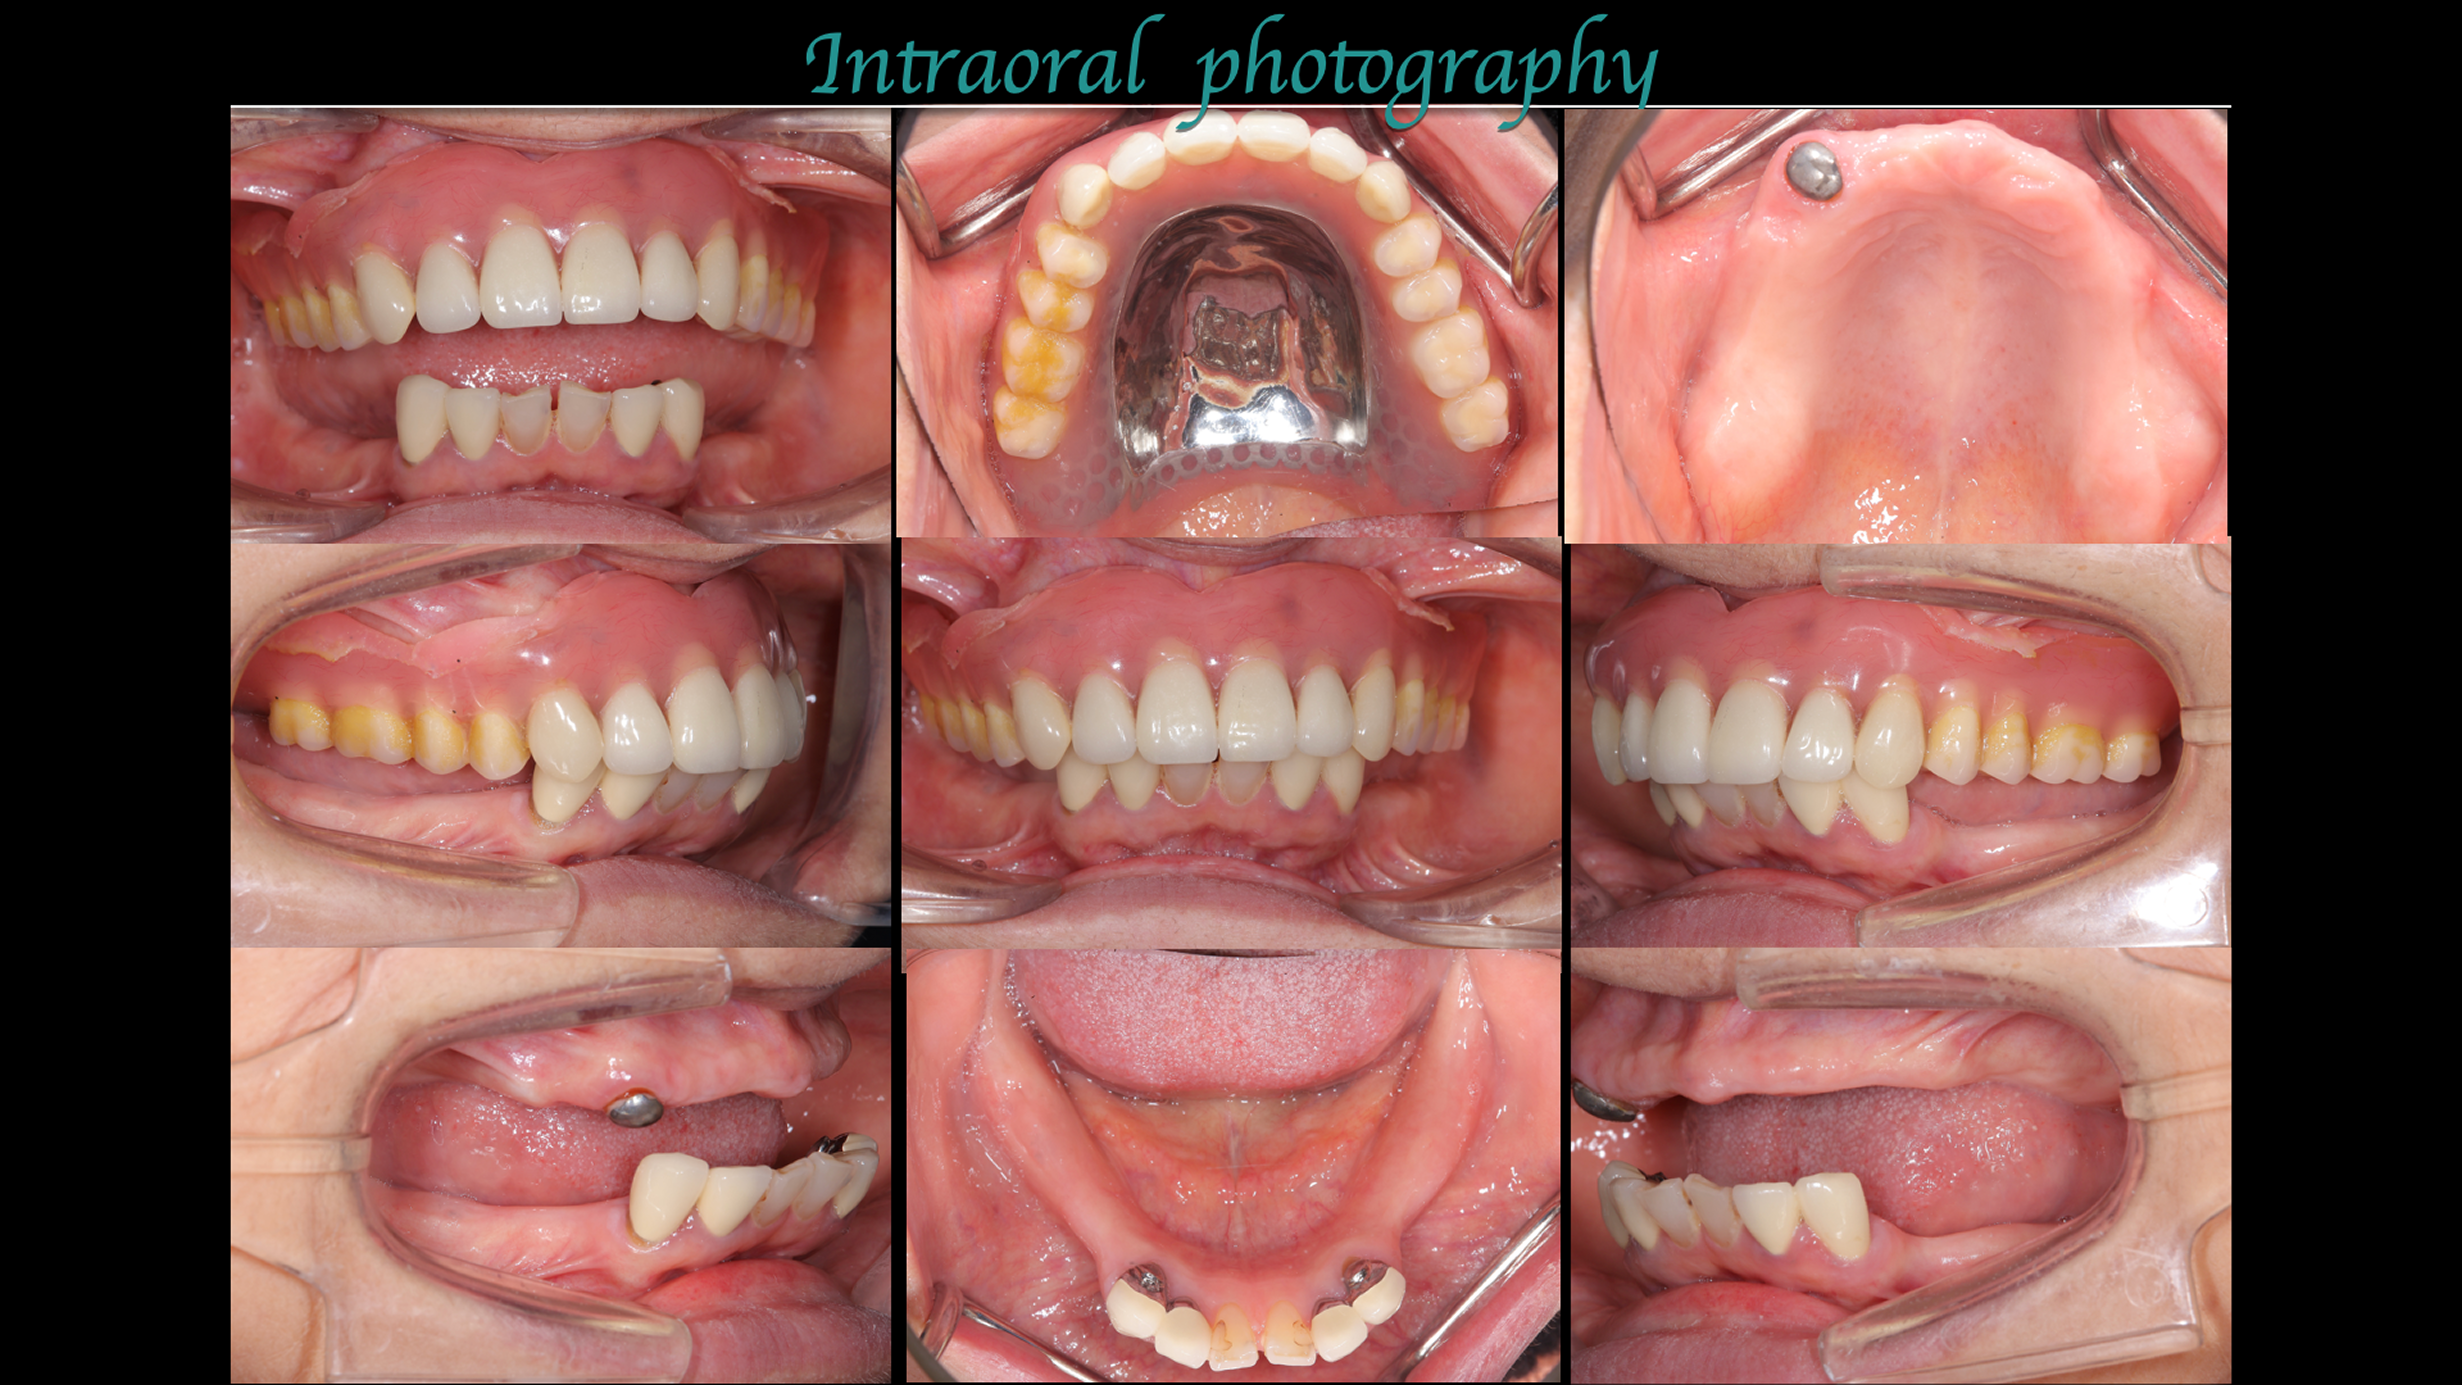

主訴:左下の歯が外れた。

治療概要:左下の歯が外れたことがきっかけで来院されました。右下と左上には歯がない状態でした。

治療前

治療後

現状残っている歯の状態から、この患者さまは「生理的咬合」であると診断し、現状噛んでいる歯の位置の修正とは行わずに、歯がないところ、歯が欠けているところを治すだけで安定すると考え治療を行っています。

デジタルシミュレーションを駆使したことで、術前の「生理的咬合である」という診断に基づいた精密な治療計画の立案が可能となりました。

治療期間はかかりましたが、計画通りに全顎の機能回復を達成し、「安心して噛める」状態を取り戻すことができました。

治療は完了しましたが、この状態を長く維持するため、今後はメンテナンスでの噛み合わせのチェックが非常に重要となります。